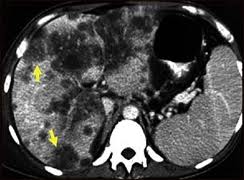

La obesidad infantil es una epidemia generalizada mundial y en paralelo con la causa no alcohólica del hígado graso (NAFLD) es la principal causa de enfermedad hepática en los niños. Los nuevos datos presentados hoy en el Congreso Internacional de Hígado de 2012 fomenta esta preocupación al mostrar que la obesidad infantil se vincula positivamente con el desarrollo de carcinoma hepatocelular – la forma más común de cáncer de hígado – en la edad adulta.

Un estudio danés controo el peso al nacer y el IMC en la edad escolar de 165.540 hombres y 160.883 mujeres nacidos entre 1930 y 1989. Los autores del estudio calcularon y compararon el riesgo de desarrollar carcinoma hepatocelular de los 252 participantes que habían desarrollado HCC en el seguimiento. A los 7 años el riesgo de carcinoma hepatocelular en desarrollo aumentó en un 1,12 por unidad de aumento en el IMC, sin embargo, a los 13 años este riesgo aumentó a 1,25. Por lo tanto, como unidades de IMC, aumentó en la edad adulta, por lo que el riesgo de desarrollar HCC. Este fue siempre similar en ambos sexos y edades.

El miembro del Comité Científico Dr. Frank Lammert comentó: «La obesidad infantil no sólo conduce al desarrollo de muchos trastornos metabólicos adversos, tales como la diabetes tipo 2 y enfermedades del corazón, sino también la enfermedad de hígado graso, que posteriormente puede dar lugar a cáncer de hígado La importancia. de mantener un índice de masa corporal saludable de la niñez no puede ser subestimada. Estos resultados alarmantes apuntan a una posible correlación entre la obesidad infantil y el desarrollo de cáncer de hígado en la edad adulta. »

Otros factores en el desarrollo de cáncer de hígado incluyen las condiciones alcohólicas, la infección por hepatitis B y C y otras enfermedades del hígado. (5) Los resultados no cambiaron cuando los participantes con estas comorbilidades fueron retirados del estudio, lo que indica que la obesidad infantil fue el principal factor en el desarrollo de carcinoma hepatocelular. Sólo en torno al 10-20% de los cánceres de hígado se puede extirpar completamente con cirugía y si esto no tiene éxito la enfermedad suele ser mortal a los 3-6 meses. (3) Por lo tanto la prevención es la mejor protección contra el desarrollo de cáncer de hígado.